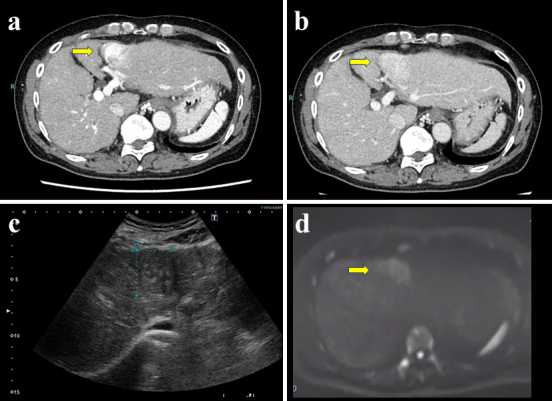

A Case of Hepatocellular Carcinoma Associated with Hepatic Sarcoidosis.

肝细胞癌合并肝结节病1例。